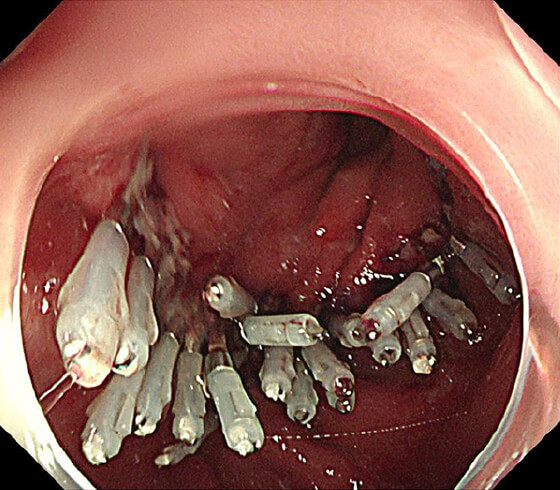

放射線療法後の遺残再発食道癌に対する光線力学的療法(PDT)も行っており、PDTの実施可能施設は九州で4施設のみ、長崎県内では当院が唯一の実施施設となっています。

PDT

PDT 5ヶ月後